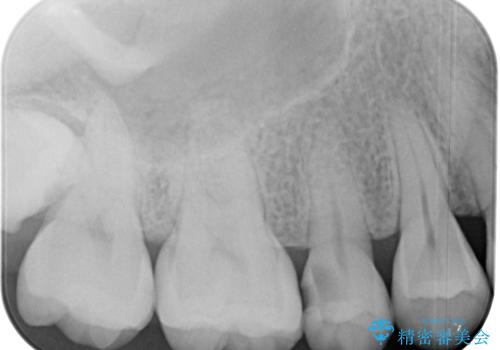

むし歯の症状のある歯は、ややしみることがある程度でしたが、レントゲン写真では非常にむし歯が大きく、神経組織に迫っている状態でした。

術前診査では神経を全て取る可能性は低いと予想されましたが、一部切除する可能性があることを伝えた上で治療を行うこととしました。

やはりむし歯は大きく、一部歯髄を切除することとなりましたが、その後は良好な経過をたどっています。